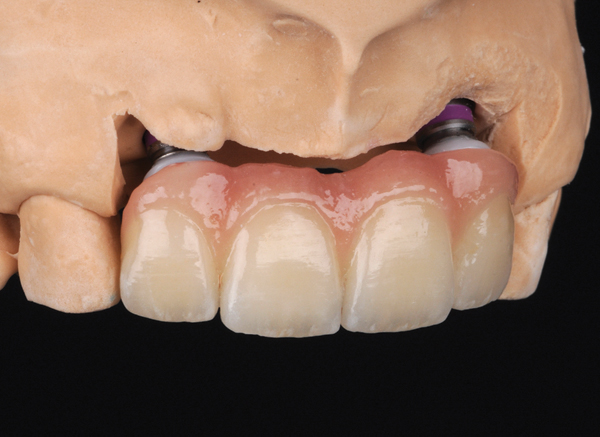

Fig 13. Porcelain-layered zirconia framework (CL-IIIb) with layered pink porcelain for the gingiva (Fig 13); final image in the mouth of the porcelain-layered zirconia framework (Fig 14) (images courtesy of Aram Torosian, MDC).

Figure 13

Fig 14. Porcelain-layered zirconia framework (CL-IIIb) with layered pink porcelain for the gingiva (Fig 13); final image in the mouth of the porcelain-layered zirconia framework (Fig 14) (images courtesy of Aram Torosian, MDC).

Figure 14

CL-IIIb high-strength 100% crystalline ceramics initially were alumina-based materials (eg, Procera®, Nobel Biocare, www.nobelbiocare.com); more recently they are zirconia-based (eg. LAVA™, 3M ESPE, www.3MESPE.com; Prettau®, Zirkonzahn, www.zirkonzahn.com). Alumina systems have proven successful for single units but are being replaced by zirconia and lithium disilicate due to the increased risk of failure in the molar region.25,26 Zirconia can also be used when significant tooth structure is missing, when high risk for flexure and stress is present, for posterior full-crown and fixed partial denture situations (Figure 13 and Figure 14), and when adhesive bonding is problematic, such as with subgingival margins.

In cases where the bond and seal cannot be maintained (ie, high-risk bonding situations, including moisture control problems, high shear and tensile stresses on bonded interfaces, and variable bonding interfaces), high-strength CL-III ceramics or metal ceramics (CL-IV, see below) are appropriate, because they can be placed using conventional cementation techniques. A concern with full-contour zirconia, however, is wear on opposing dentition.27

Whether alumina or zirconia, these materials demonstrate greater strength than CL-I and CL-II materials and can be used to fabricate a core substructure to replace metal. However, they are more opaque due to their greater crystalline content, which detracts from overall esthetics. They are therefore layered with porcelain,28 allowing these materials to offer both superior strength and improved esthetic results.28 CL-III high-strength ceramics require a thickness of 1.2 mm to 1.5 mm, depending on the substrate color.20,26